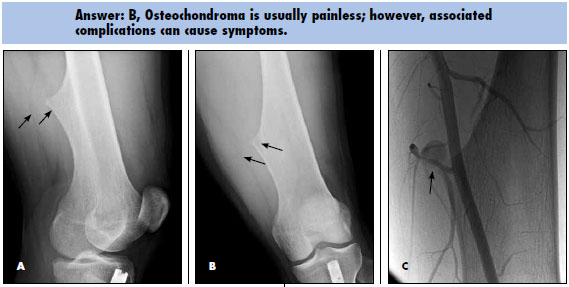

Along with mild soft tissue swelling in the distal thigh, the radiographs show an eccentric cortical outgrowth from the distal femur, directed away from the joint (A and B). The rod and nail present in the proximal tibia is related to a prior fracture.

The image findings are classic for osteochondroma. This cartilage-capped bony projection may arise from the external surface of any bone of cartilaginous origin. However, osteochondromas most commonly occur in the long bones. Similar to the physeal growth plate, an osteochondroma ceases to grow at puberty; cartilage decreases in thickness and undergoes ossification.

This patient underwent further evaluation with ultrasonography of the left thigh, which showed a pseudoaneurysm of the superficial femoral artery. This finding explained the acute onset of pain. A conventional angiogram confirmed the ultrasonography findings and showed the pseudoaneurysm coming off a branch vessel of the distal superficial femoral artery (C). Coil embolization of the pseudoaneurysm was performed.